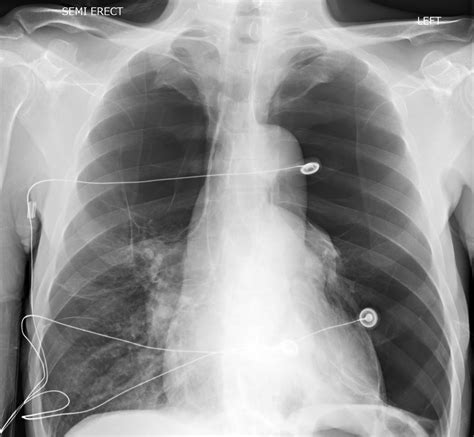

Diagnostic Procedures

Diagnosis begins with a thorough medical history and physical examination. However, imaging is essential to confirm Bullous Lung Disease. High-resolution Computed Tomography (HRCT) is considered the gold standard for visualizing bullae. It allows physicians to determine if the bullae are localized or widespread and whether they are compressing functional lung tissue. Pulmonary function tests (PFTs) are also conducted to measure lung capacity and identify the degree of airflow obstruction.